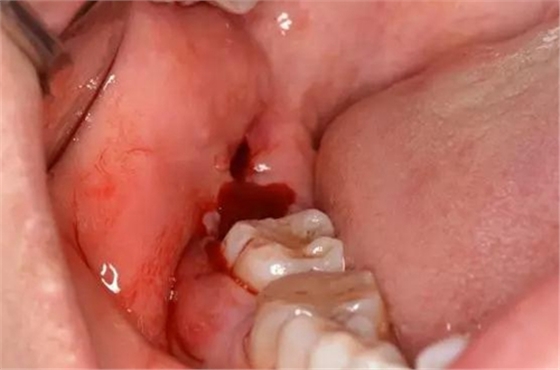

圖11.清理并復(fù)位拔牙創(chuàng)

圖12.遠(yuǎn)中縫合一針